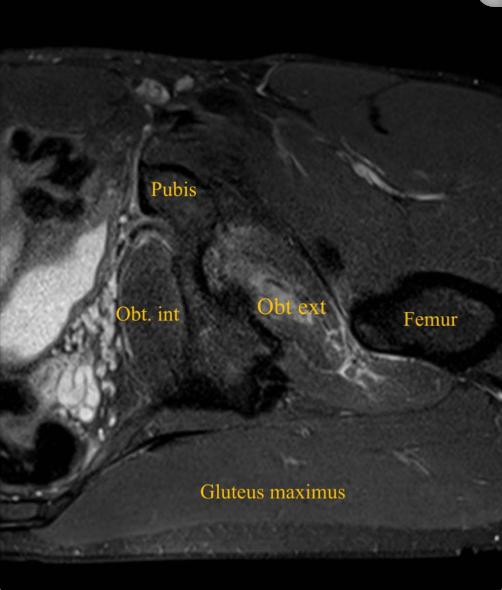

患者男性,32岁,职业足球运动员,在赛季训练期间出现急性左腹股沟疼痛和臀部疼痛,视觉模拟量表(VAS)评分为8/10,这是由髋关节的快速和负重内旋运动引起的,髋关节和膝关节弯曲约90度,在快速改变方向和切入进攻的过程中,功能立即丧失。患者否认腿部有任何麻木、虚弱或辐射性疼痛。体检时,没有瘀伤、瘀斑、水肿或肿胀。坐骨结节触诊有轻微疼痛和压痛。在内收肌、腘绳肌或髂腰肌的特定测试中未发现异常。膝关节和髋关节处于90°时髋关节主动外旋和被动内旋都会引起髋关节疼痛。这位运动员跛行。对左髋关节进行x线检查,以排除髋关节病变,包括股骨髋臼撞击。核磁共振成像显示左侧闭孔外肌的后腱膜下/肌腱膜撕裂,从耻骨起点延伸至外侧肌腱连接处,横断面测量为10 cm,前后径为3.5 cm,伴有股方肌和闭孔内肌间质水肿(图1-4)。

图3、左大腿轴向(STIR) MRI显示左闭孔外撕裂